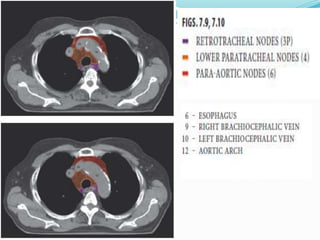

The International Association for the

 14 LN stations reorganized into 7 zones

 Supraclavicular zone

 Upper zone

 AP zone

 Subcarinal zone

 Lower zone

 Hilar zone

 Peripheral zone

Lymph nodal stations in ca lung